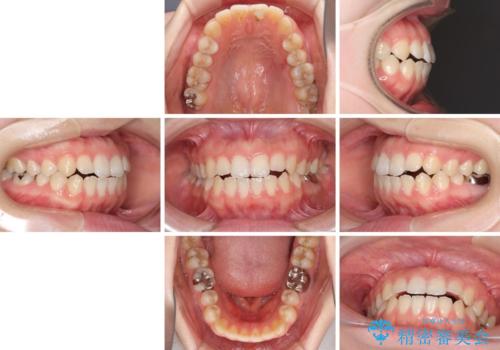

- 口元の膨らみが気になるとのことで来院された患者様です。

非抜歯で口元の突出感を少し改善させる治療も提案しましたが、最大限口元を引っ込めたいとのことでした。

上下左右第一小臼歯4本を抜歯し、ワイヤー装置により矯正治療を行うこととしました。

治療は順調に進み、予定された期間で終了することができました。

装置除去後には、スッキリとした口元となり、大変満足していただきました。